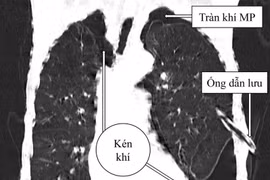

Kén khí phổi là bệnh lý ít gặp và thường không gây ra những triệu chứng rõ ràng, nhưng nếu không được phát hiện và điều trị kịp thời, kén có thể vỡ, dẫn tới tràn khí màng phổi và gây nguy hiểm cho người bệnh.

Kén khí phổi nếu không phát hiện, phẫu thuật kịp thời sẽ gây xẹp cả phổi ở bên có kén, đẩy trung thất ép cả phổi bên đối diện, đưa đến hậu quả là suy hô hấp rất nặng nề. Kén vỡ gây tràn khí màng phổi dễ tử vong.

Sau thời gian dài bị đau tức ngực, nữ bệnh nhân đã được các bác sĩ tại bệnh viện đa khoa tỉnh Phú Thọ phẫu thuật cắt khối kén khí phổi khổng lồ (kích thước khoảng 13x7cm).

Bệnh nhân bị vỡ kén khí và đứt dây chằng đỉnh phổi chảy nhiều máu giữa lằn ranh cái chết và sự sống chỉ trong gang tấc đã được cứu sống bằng kỹ thuật nội soi toàn bộ 3D.